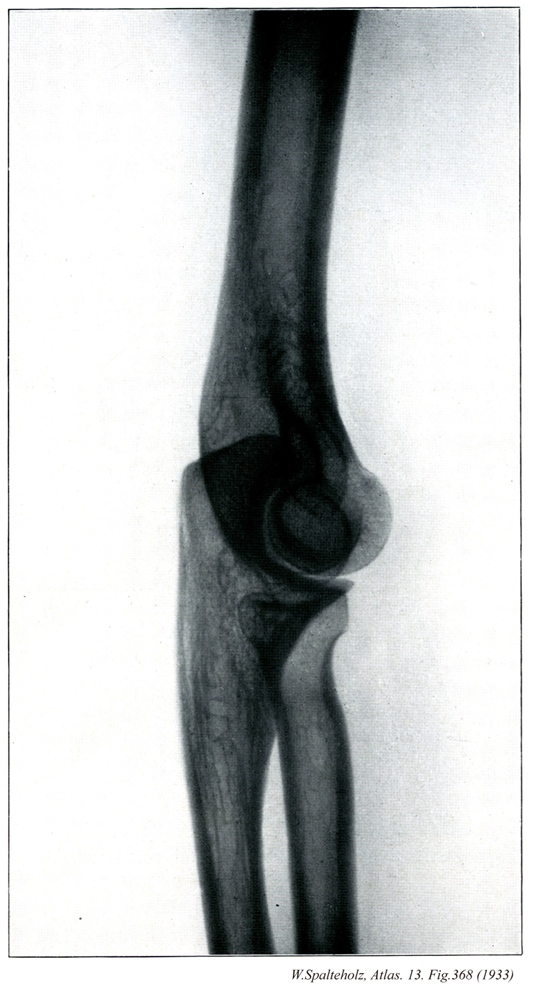

368_00【Elbow joint肘関節 Articulatio cubiti】 Joint formed by the humerus, radius, and ulna.

→(肘関節は上腕骨と橈骨、尺骨の3骨の間に生じた複関節で、肘の屈伸を行う。したがって分類状は1軸性の蝶番関節とみることができる。上腕骨滑車と尺骨の滑車切痕との間の腕尺関節、上腕骨小頭と橈骨頭との間の腕橈切痕との間の上頭尺関節が共通の関節包におおわれる。しかし後者は機能的には下橈尺関節とともに前腕の回旋に関係するので、前2者とは別に記載するのが通例である。上腕骨の内側および外側上顆は関節包におおわれない。関節包の内側と外側はそれぞれ内側側副靱帯および外側側副靱帯によって補強される。橈骨輪状靱帯は、関節包の内面が肥厚した幅約1cmの靱帯で、尺骨の橈骨切痕の前縁からおこり、橈骨の関節環状面を輪状にとりまいたのち、再び尺骨の橈骨切痕の後縁につく。この靱帯の関節腔に面した部分は軟骨性となり、尺骨の橈骨切痕とともに上橈尺関節における関節窩を形成する。肘関節における屈伸運動の役割を演ずるのは腕尺関節である。しかし上腕骨滑車の内側部の直径が外側部のそれよりやや大きいため、肘を伸ばすと、その時の尺骨の長軸は、上腕骨長軸よりも外方へ約10~20°の傾きを示す。この角をcarrying angleという。しかし肘を曲げたときは、両骨の長軸は重なり合う。)